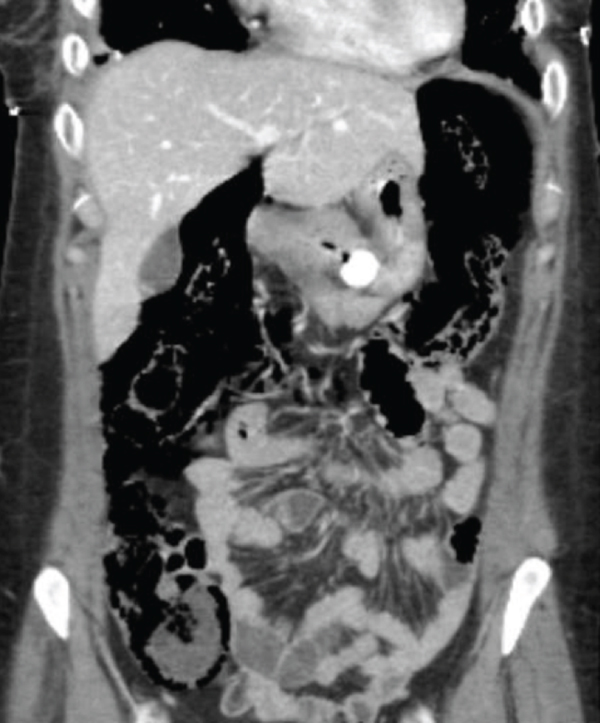

Imaging findings of pneumatosis intestinalis posttransplant are unique as compared to PI seen in other scenarios such as bowel ischemia. PI in posttransplant patients has a bubble-like/expansile appearance with a significant amount of air within the bowel wall (Figures 1 and 2). In these patients, it is helpful to view the pneumatosis on lung windows in order to properly assess its extent (Figure 3). In contrast, for PI in a patient with intestinal ischemia (Figure 4), imaging findings show more of a thin rim of gas bubbles within the submucosa without the expansile appearance. Although posttransplant PI can appear as a thin layer of gas, it would be unusual for intestinal ischemia to appear as bubble-like/expansile. Thus, if the bubble-like/expansive appearance of PI is seen, it may support a benign etiology and clinical course.

(a)

(b)

(c)